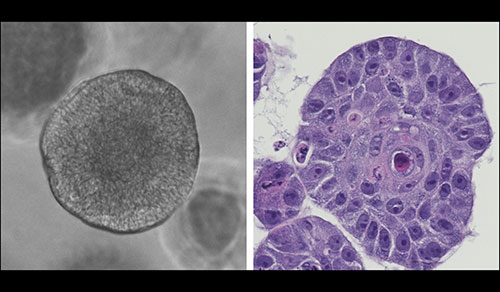

Results from a new multi-center study, led by oncologists at NewYork-Presbyterian and Weill Cornell Medicine, has described for the first time a key biomarker – absolute lymphocyte count (ALC) – that has the potential to predict therapeutic response to chimeric antigen receptor (CAR) T-cell immunotherapy for patients with relapsed/refractory multiple myeloma. While this FDA-approved treatment is widely used, until now there has not been a way to predict whether B-cell maturation antigen (BCMA) CAR T-cell therapy would elicit a good response.